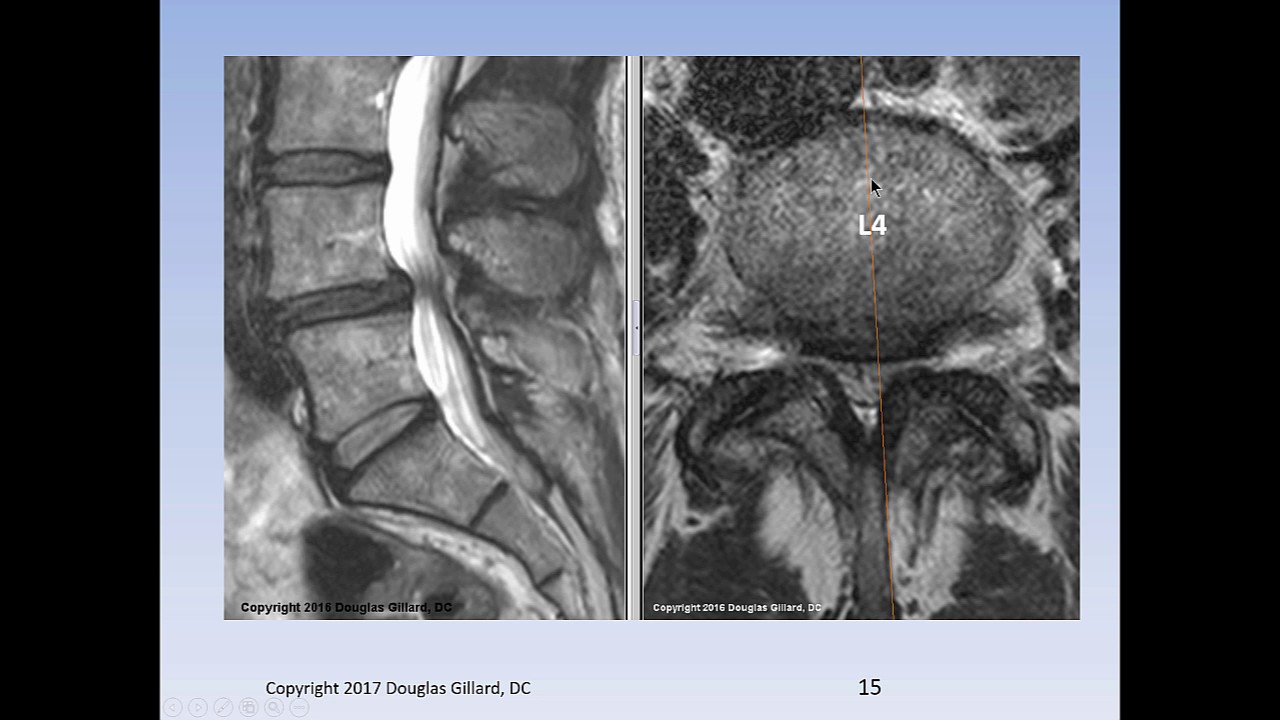

que interessante E aí assim uma das coisas que talvez explique né Essa problemática todo do exame de imagem precoce na do lombar é que a correlação dos achados de imagem com a queixa Clínica não é boa e para exemplificar isso tem um trabalho famoso do New England de 1994 que avaliou ressonância magnética de coluna em pacientes sem do lombar eles pegaram 98 pessoas assintomáticas e viram que somente 36% dessas pessoas tinham uma ressonância normal ou seja mais da metade vai ter ressonância alterada tá sem sintomas né Acho que em ortopedia isso é muito comum né

João então não somente nas dores de coluna ah dores lombares mas doem joelho quadril etc é muito comum a gente encontrar essa dissociação Clínico radiológica exato isso vai ao encontro até num coisa que eu falei na primeira armadilha que isso Foca no aspecto patológico o paciente se agarra naquela alteração e reforça O enfrentamento negativo da queixa sim né é o bico de papagaio né o famoso bico de papagaio da ele vê protusões discais abaulamentos discais que tem pouca relação com a com a queixa Clínica E isso não melhora o quadro e e tá associado com